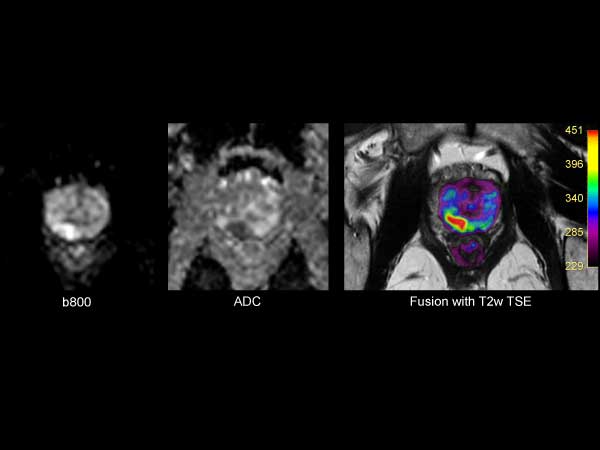

73 year old male with known prostate carcinoma. Size of 5mm, located in right posterior region. Patient is under active surveillance. Request for MR-guided prostate biopsy to re-evaluate.